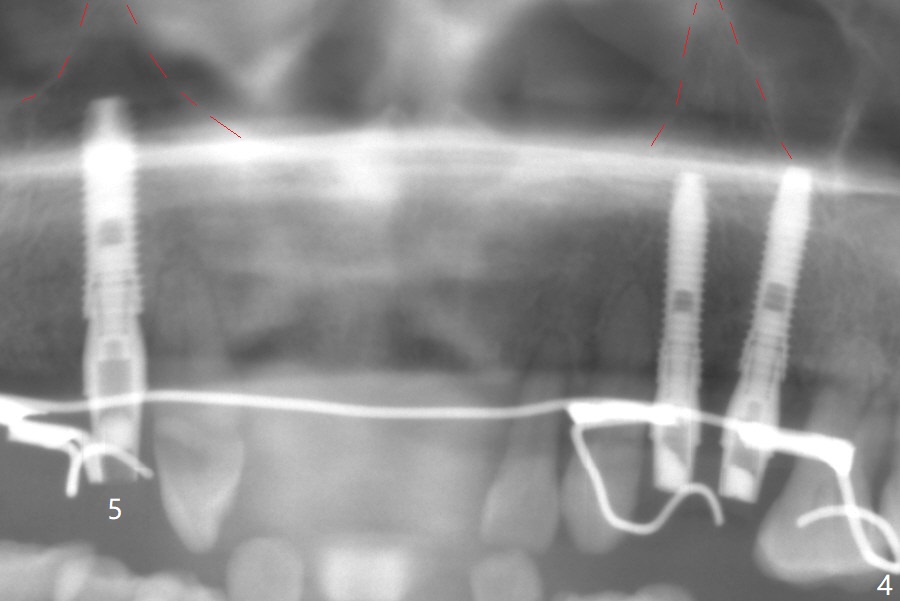

A 66-year-old woman returns to office requesting implant placement at #12 and 13 at an appointment supposed for #5 impression. Depth of osteotomy is 20 mm (gingival level, Fig.1 ( 2mm)). After correction of trajectory at #12 and 3 mm drill for 16 mm at the sites, two of 3.8x16 mm implant are placed with insertion torques of 35 and 15 Ncm, respectively (Fig.2). Before and after change into shorter abutments (4.5x4(4) and (5)), Vera Graft is placed (Fig.3 *). To increase stability, either increase the diameter (4 (Fig.4 at #5) or 4.5 mm instead of 3.8) or length of the implants (red dashed line: sinus floor). Or use dummy implants. The allograft appears to have been incorporated into the host bone nearly 4 months postop (Fig.5). The abutment of the isolate implant at #5 becomes loose twice (Fig.4). To reduce the chance of abutment loosening at #12 and 13, can you make splinted crowns? If the two separate crowns have been fabricated, can you make a slot (with light undercut) in the proximal area of each crown (Fig.6 (occlusal view): S) in addition to access hole (A)? After cementation, composite will be placed in the slots (lock) so that the crowns will not rotate and become loose.